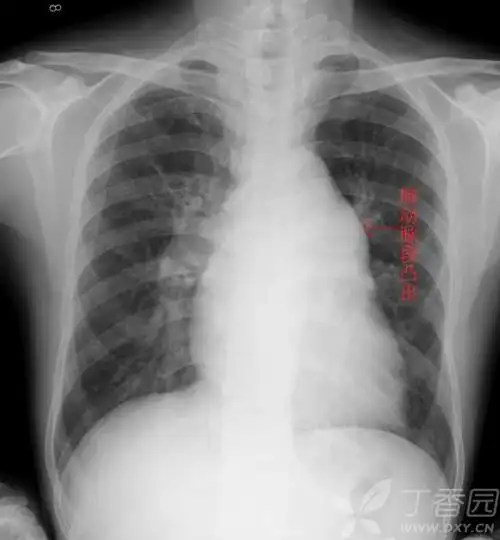

普大型心梨形心靴形心的片子究竟怎么看啊丁香园

阅读x线胸片,这是一个靴形心脏的胸片.